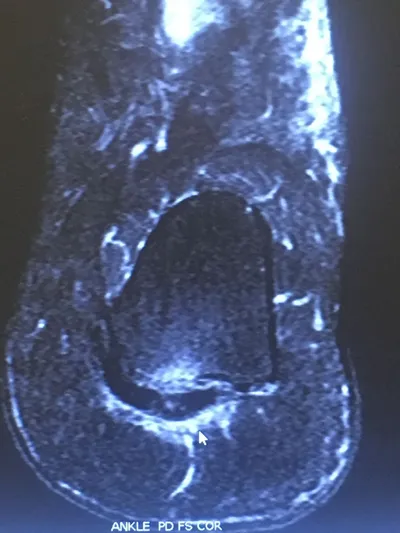

MRI of Severe Plantar Fasciitis of the Medial and Central Band. The bands of the plantar fascia are thickened and there is swelling around the soft tissue of where the fascia inserts in the heel as well in the heel bone itself. On this MRI, the white is inflammation.The arrow points to the thickend and inflammed ligament.